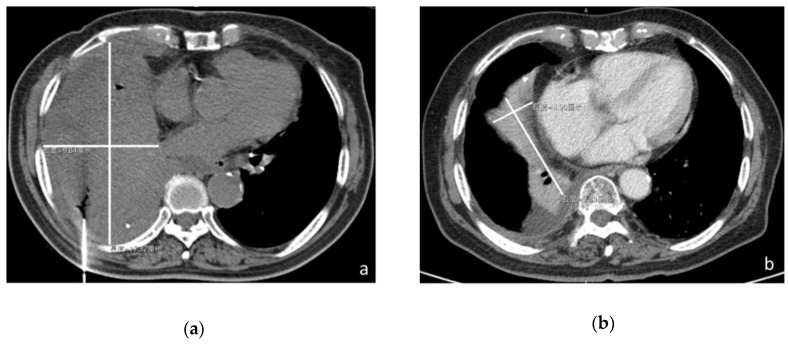

Figure 1 Dish-cultured Antrodia cinnamomea (DAC) shrinks the tumor in a cancer patient with administration for only 6 months. CT image of the patient (a) in December 2015 revealed a huge tumor (17.26 × 9.78 cm in the largest dimension) in the right lower lung and (b) in July 2017 showed the tumor mass remarkably reduced in size (8.89 × 3.90 cm in the largest dimension).